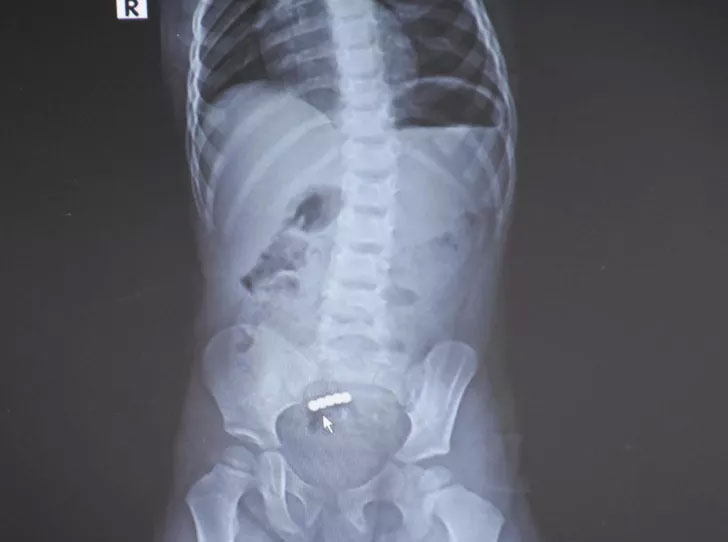

İzmir’İn Aliağa ilçesinde yaşayan, 2 çocukları olan mühendis Ali Güler ile muhasebeci Nurdan Güler’in 2,5 yaşındaki kızları Cemre, 6 Mart’ta, ağabeyiyle evde oynarken oyuncak mıknatıs yuttu. Şiddetli karın ağrısı ve kusma şikayetiyle Kent Hastanesi’ne getirilen Cemre’ye çekilen filmde, bağırsaklarında 5 küçük mıknatıs tespit edildi. Ameliyata alınan Cemre, operasyonun ardından sağlığına kavuştu.

Ameliyatı yapan Doç. Dr. Tunç Özdemir de 1 yıl içinde mıknatıs yutan 2’nci çocuk vakasıyla karşılaştıklarını belirterek bu kazaların ölümcül sonuçlara yol açabildiğine dikkati çekti. Cemre’nin bağırsağından yaklaşık 10 santimetrelik kısmı almak zorunda kaldıklarını söyleyen Özdemir, “Hastayı gördüğümde şiddetli karın ağrısı vardı, kusuyordu. Daha önceki deneyimlerim dolayısıyla çoklu mıknatıs yuttuğu için aşağı yukarı ne olduğunu tahmin ettim. Genellikle bağırsak tıkanıklığı ve bağırsak delinmesi tablosuyla karşılaşıyoruz. Aileye kısa sürede ameliyat edilmesi gerektiğini söyledik. 2,5 yaşında bir çocuk için bağırsak tıkanıklığı ve delinmesi çok ağır bir tabloya neden olur. Ameliyatta tahmin ettiğimiz gibi 4 mıknatıs bir bağırsakta, 1 mıknatıs diğer bağırsakta dururken birbirlerini birbirlerini bulmuşlar. Mıknatıslar çok güçlü olduğu için aradaki iki bağırsak duvarı zamanla eriyip mıknatısların birbirine bağlanmasına neden olmuş. Bir bağırsakta 3 delik vardı. Yaklaşık 10 santimetre kadar bağırsağı çıkarmak durumunda kaldık, diğer tarafta ise bağırsaktaki deliği onardık” açıklamalarında bulundu.